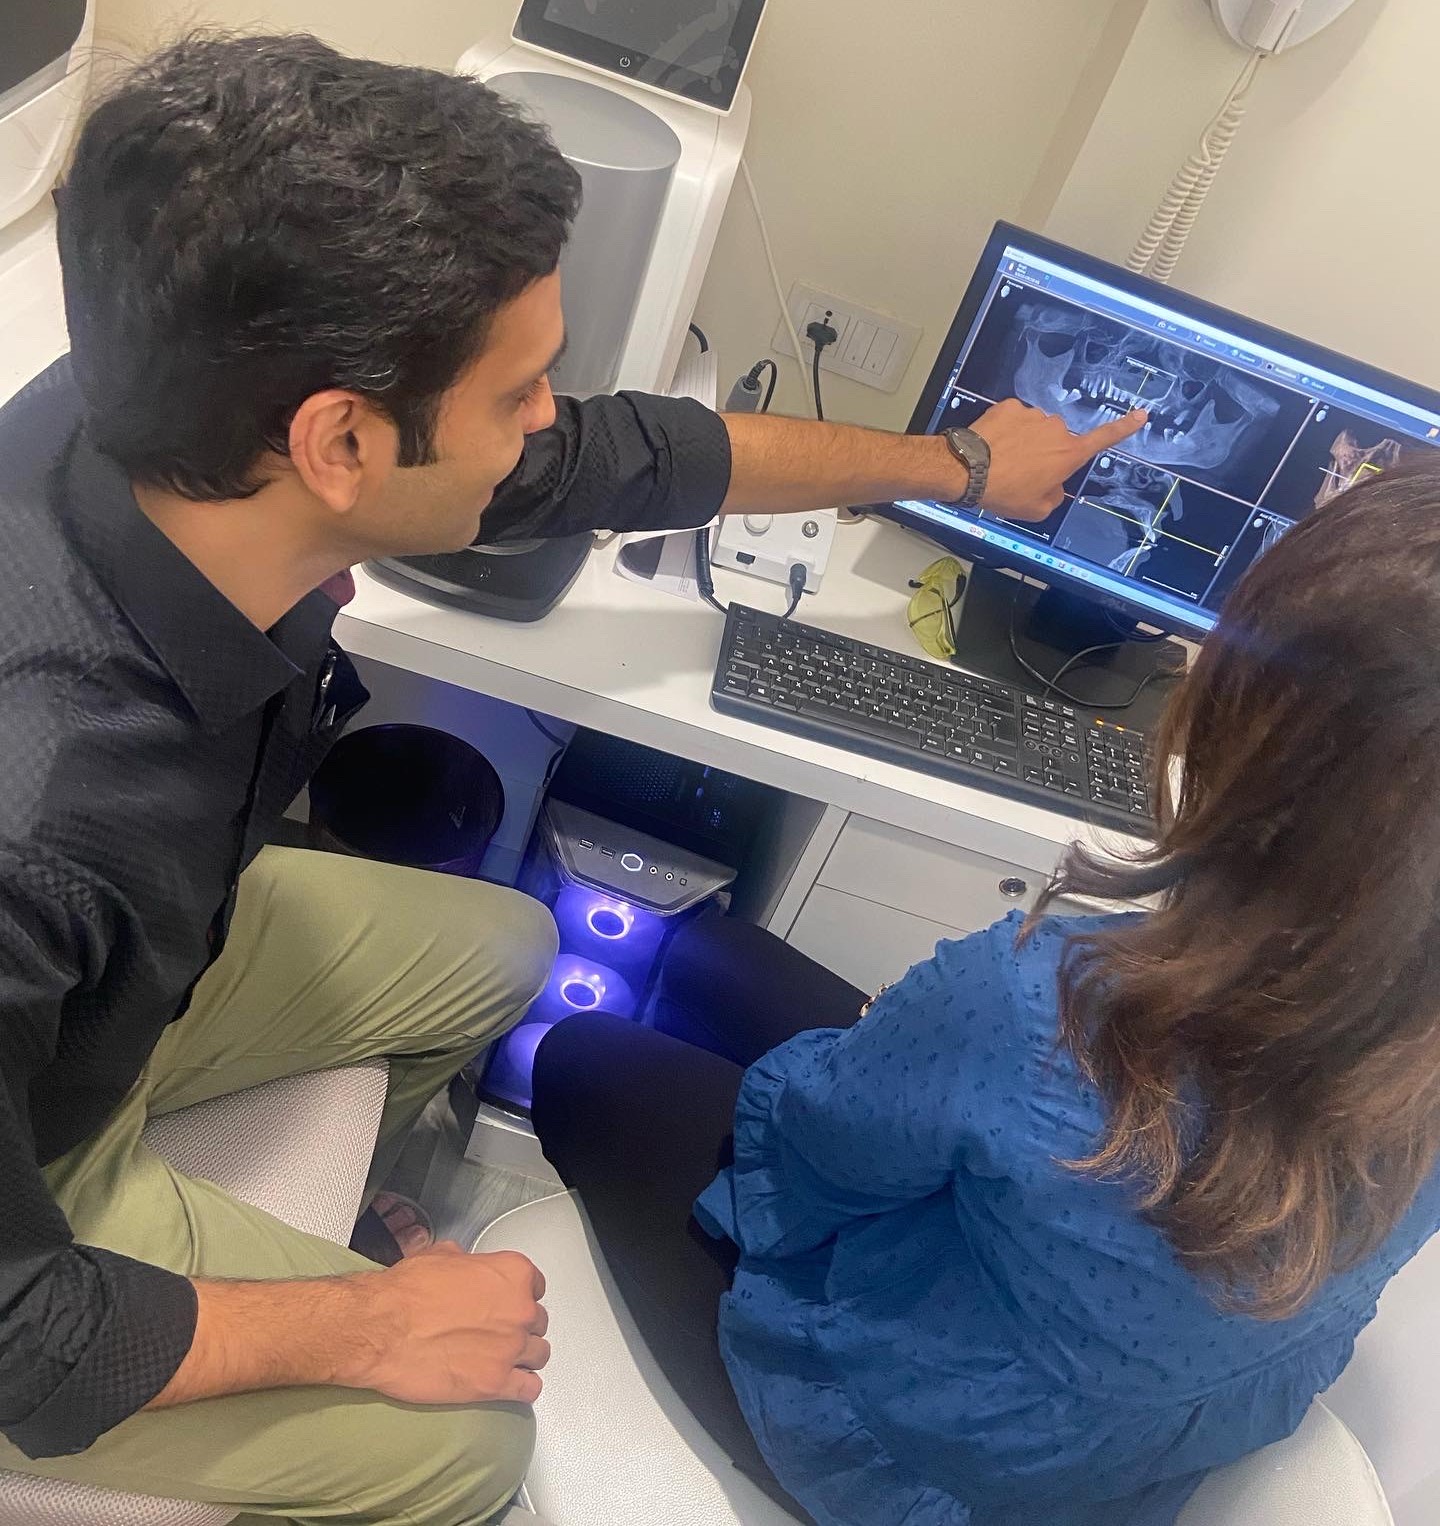

Our experienced team is committed to providing personalized care and addressing any concerns you may have throughout your visit.